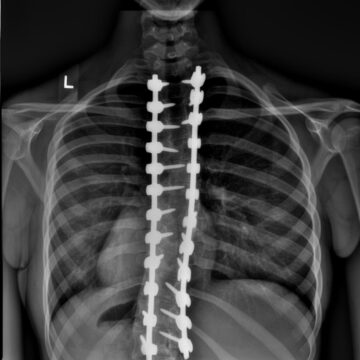

جراحة اعوجاج العمود الفقري: 8 حقائق صادمة لا يخبرك بها الطبيب قبل اتخاذ القرار عندما نسمع عن جراحة اعوجاج العمود الفقري، قد يعتقد بعض الأهل والمراهقين أنها “الحل السحري” لإعادة العمود الفقري إلى طبيعته

مستويات المعادن في الدم بعد جراحة أو استخدام حزام اعوجاج العمود الفقري يتساءل كثير من المرضى وأولياء الأمور عن التأثيرات طويلة المدى لجراحة اعوجاج العمود الفقري عند المراهقين، خاصة عندما يتم تثبيت قضبان معدنية